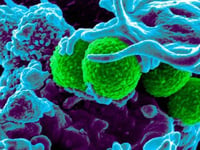

El equipo de investigadores de la Universidad de California en San Diego ha desarrollado una vacuna que apunta a desencadenar una respuesta inmunitaria…